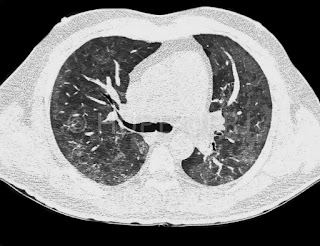

Doente jovem com diagnóstico de linfoma, duas tomografias de tórax, a segunda realizada um mês após, com piora nítida (nódulos e massas pulmonares, massa axilar esquerda). Evolução arrastada de espondilodiscite (destruição de vários corpos contíguos e coleção que se dissemina para região paravertebral e iliopsoas). Diversas lesões ósseas no ilíaco.

Tomografia inicial:

Evolução após um mês: